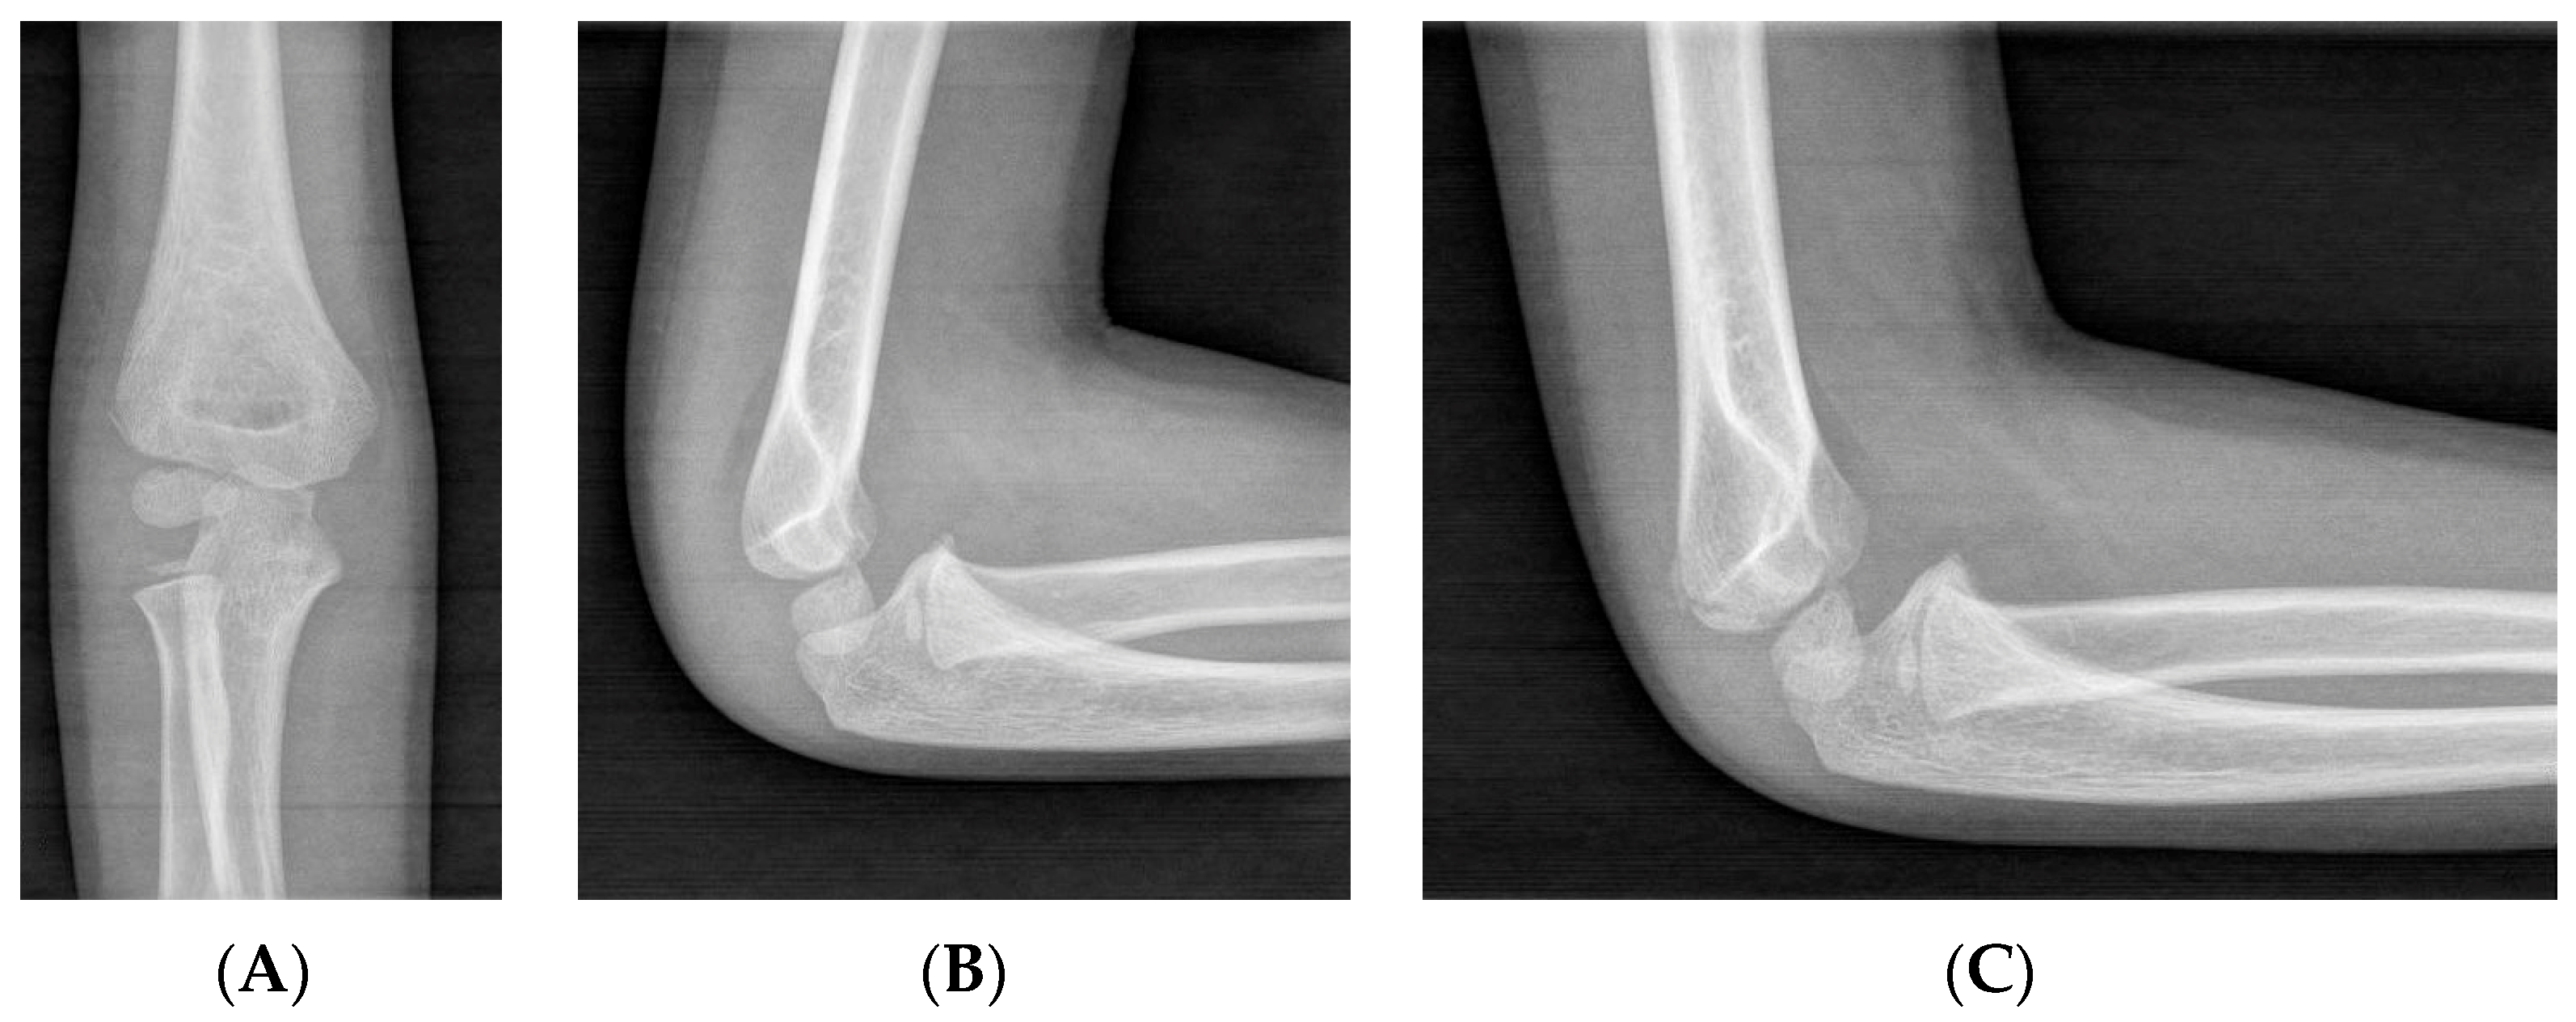

2.2.1. X-Rays